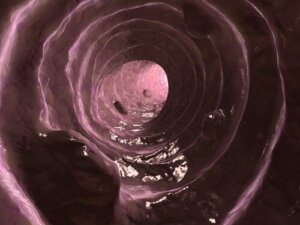

Slim er et stoff som skilles ut av tarmslimhinnen – likt det som produseres av respiratorisk epitel – hvis funksjon er å holde slimhinnen i tykktarmen smurt og fuktig.